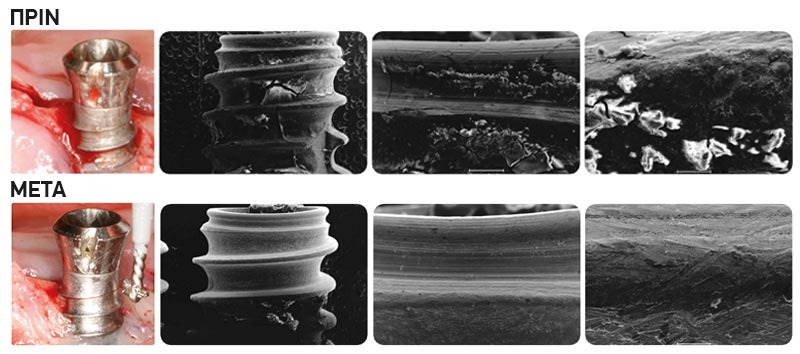

- Η τραχύτητα της επιφάνειας του εμφυτεύματος, διατηρείται μετά από τη χρήση του iBrush